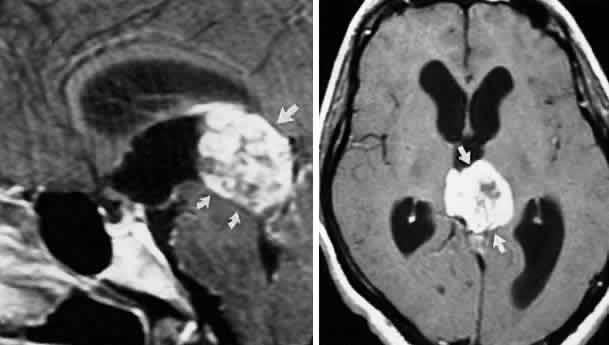

FASCICULAR LESIONS Deficits of the oculomotor fasciculus are usually identified by the accompanying brain stem signs. Oculomotor palsy with contralateral hemiplegia (Weber syndrome) indicates involvement of the corticospinal tracts. Contralateral ataxia and intention tremor (Benedikt syndrome) indicates involvement of the red nucleus (see Fig. 2). Nothnagel syndrome is an eponym given when signs of both Weber and Benedikt syndromes are present. Midbrain vascular accidents account for most fascicular defects. Ksiazek84 shed some light on the fascicular arrangement of the oculomotor nerve based on two patients with partial oculomotor paresis, each with pupillary mydriasis, significant inferior rectus paresis, and medial rectus paresis. Neuroimaging revealed a lesion in the fascicular portion of the nerve, thus indicating the proximity of these fibers in the fasciculus. Monocular elevator paresis (superior rectus and inferior oblique) in mass compression of the oculomotor fasciculus has also been reported.85 In this regard, Castro and associates86 proposed the mediolateral somatotopy of the oculomotor fascicular fibers within the mesencephalon with the inferior oblique and superior rectus muscles being most lateral, and the pupilloconstrictor fibers and inferior rectus being most medial. The levator palpebrae fascicles are in an intermediate location between the superior rectus and medial rectus fascicles. INTERPEDUNCULAR LESIONS Basal lesions, including the rare rostral basilar artery aneurysm, may encroach on the oculomotor nerves as they exit in the interpeduncular space. Such slow-growing aneurysms, either saccular or fusiform, may present as partial oculomotor palsies with or without involvement of pyramidal tracts, and without subarachnoid hemorrhage.87 Aneurysms of the posterior communicating artery, on the other hand, are probably the most common lesions causing acute spontaneous oculomotor palsies (Fig. 12). According to Hyland and Barnett,88 the oculomotor palsy that occurs with posterior communicating aneurysm is not necessarily due to mass effect per se, but rather is attributed to hemorrhage that suddenly enlarges the aneurysmal sac to which the oculomotor nerve is adherent, or to hemorrhage into the substance of the nerve itself. Most patients present, therefore, with an intensely painful, complete unilateral oculomotor palsy in association with other signs and symptoms of subarachnoid hemorrhage. Few patients with symptomatic posterior communicating aneurysms are found in office waiting rooms: they are usually obtunded or comatose in emergency rooms. Involvement of pupillary fibers is such a consistent finding in third nerve palsies due to bleeding aneurysms that most clinicians concur in this useful dictum: a pupil-sparing, but otherwise complete, third nerve palsy is very unlikely to be due to posterior communicating aneurysms. Careful pupil evaluation may disclose subtle abnormalities in “apparent pupil-sparing,” especially in cases of aberrant regeneration or with chronic cavernous sinus lesions. Generally, in patients at least 50 years of age or older, an acute, isolated, painful oculomotor palsy that spares the pupil is caused by intraneural ischemia; nevertheless, these patients must be carefully observed for further evolution. In our opinion, an acute complete oculomotor palsy with moderate to major mydriasis, even when diabetes is present, is an indication for cerebral arteriography. It should be emphasized that magnetic resonance angiography may not detect aneurysms smaller than 3 to 4 mm.89 The clinical management of patients with relative pupil-sparing third nerve palsies remains in debate. Observation alone arguably is appropriate management of such patients; however, since practically every conceivable combination of partial ophthalmoplegia and pupillary abnormality has been reported in aneurysmal compression of the third nerve, it is better to err on the side of caution and perform angiography more frequently. It is incumbent upon the physician to evaluate carefully the proportion of ophthalmoplegia and ptosis in relation to the degree of pupillary abnormality when deciding appropriate workup of these patients. Again, the increasing sensitivity of magnetic resonance angiography has not yet entirely replaced formal angiography. Certainly, neurosurgical intervention requires conventional cerebral arteriography before surgical treatment. Capó and colleagues90 pointed out that the interval from onset to maximal ophthalmoplegia does not differentiate between microvascular (3.3 days) and aneurysm (3 days), but that failure to recover within 4 to 8 weeks requires further evaluation. Other partial oculomotor palsies occur regularly with cavernous sinus masses and parasellar syndromes (see below), accompanied by variable pupillary findings. Furthermore, both acute and chronic lesions may produce incomplete palsy of the superior division (supplying levator palpebrae and superior rectus muscles) or of the inferior division (medial and inferior recti, inferior oblique and pupillomotor fibers). If pain or first trigeminal division numbness are absent, and if the pupil is uninvolved, such fractional oculomotor pareses are regularly misinterpreted as myasthenia or local orbital inflammations. Guy et al91 described five patients with isolated ptosis and elevator paresis in abduction, consistent with selective “superior division” involvement. They also discussed five previously reported cases with the following respective diagnoses: (1) intracavernous aneurysm (usually with associated Horner's syndrome) and basilar artery aneurysm; (2) diabetic ophthalmoplegia; (3) meningitis; (4) dural lymphoma; and (5) postsurgical manipulation of parasellar structures. In essence, there was little anatomic correlation with the physical separation into superior and inferior oculomotor trunks that occurs in the cavernous sinus. Moreover, two patients sustained superior division palsies during surgical manipulation of the subarachnoidal portion of the oculomotor nerve trunk. A number of cases of inferior rectus paresis, isolated or in combination with ipsilateral or contralateral superior rectus paresis, have been construed as focal lesions involving the rostral portion of the oculomotor nuclear complex.80–82 Oculomotor palsy following head trauma is not rare, but probably occurs less frequently than traumatic fourth nerve palsies. As a rule, such closed-head injury causes loss of consciousness and is accompanied by skull fracture, but this is not invariable. Injury to the ocular motor nerves in road accidents was studied by Heinze,92 who dissected the cadavers of 21 fatal cases. He found that the relationship of frontal or temporal fractures to neural damage was unpredictable. In fact, intact nerves were encountered adjacent to gross fracture sites. The oculomotor nerve was damaged at three locations: (1) avulsion of the rootlets at their ventral exit from the brain stem; (2) contusion necrosis of the most proximal portion of the nerve trunk; and (3) intraneural and perineural hemorrhage of the nerve trunks at the level of the superior orbital fissure. Of great interest are Heinze's findings of focal hemorrhages in extraocular muscles, usually associated with fractured orbital bones. Eyster et al93 reported three patients with large basicranial tumors, who presented with oculomotor palsies precipitated by mild blows to the head that were insufficient to cause fracture or loss of consciousness. The oculomotor nerves were encased and stretched by tumor, which apparently rendered these tethered nerves vulnerable when innocent head blows abruptly shifted the brain. The authors pointed out that such atypical presentations of intracranial tumors may further mimic aneurysms, since subarachnoid hemorrhage does occasionally occur with tumors. Neetens94 reported an additional three cases of oculomotor nerve palsies after minor trauma in the presence of basal intracranial tumors; the trochlear nerve was involved in all three cases, and in two cases the oculomotor nerve was partially affected. Walter et al95 reported two instances of minor head trauma resulting in complete third nerve palsies attributed to occult posterior communicating artery aneurysms. We have seen a 45-year-old school teacher who experienced an immediate right abducens palsy when playfully slapped on the back of the head; within weeks, other cranial nerve palsies announced the presence of diffuse meningeal spread of carcinoma. In the United States, basilar meningitis is rare, but was formerly encountered with tuberculosis and syphilis. When the third nerve is involved in such cases, progressive defects are the rule and other cranial nerve palsies are commonly found. Oculomotor palsy may especially occur with meningitides in infants, including instances of viral and bacterial (e.g., Streptococcus pneumoniae, Haemophilus influenzae) infections.96 Oculomotor nerve compression by the proximal segment of the posterior cerebral artery, or by the uncus against the petroclinoid ligament, can be seen with increasing cerebral edema or with an ipsilateral expanding supratentorial mass, and it is often heralded by unilateral pupillary dilation (Hutchinson pupil). Progression rapidly leads to complete ocular motor nerve palsy. Keane97 reviewed the ocular motor signs of tentorial herniation, which include anisocoria and parasympathetic pupillary abnormalities, unilateral or bilateral ptosis, internuclear ophthalmoplegia, vertical gaze paresis, and partial third nerve palsies. CAVERNOUS SINUS LESIONS The oculomotor nerve may be involved by inflammatory disease, tumor, aneurysm, arteriovenous fistula, or thrombosis at the level of the cavernous sinus. The third nerve is usually involved in combination with the fourth, sixth, and ophthalmictrigeminal nerves, and accompanying sympathetic paresis may minimize pupillary dilation. The syndrome of the cavernous sinus, therefore, includes multiple ocular motor nerve palsies and pain or numbness in the first trigeminal division. In practice, lesions involving primarily the superior orbital fissure produce signs and symptoms that, with the possible exception of proptosis, cannot be distinguished from those of the anterior cavernous sinus. In particular, dural carotid cavernous fistulas that drain primarily into the inferior petrosal sinus may cause third nerve pareses without significant orbital congestion.98 Third nerve palsies due to lesions in the cavernous sinus tend to be partial in that all muscles innervated by the oculomotor branches need not be involved. This is especially true of pupillomotor fibers, such that the pupil may be normal or minimally involved. This “pupil- sparing” is offhandedly attributed to the superimposition of sympathetic paresis (Horner syndrome), but appropriate pharmacologic tests rarely substantiate this explanation (see below, Parasellar Syndrome). More likely, slowly expanding masses (e.g., infraclinoid aneurysm, meningioma) functionally spare the pupilloconstrictor fibers in the intracavernous portion of the oculomotor nerve. In addition, the levator, superior, inferior, and medial recti may be involved in unequal degrees, but progressive paresis evolves. (Once again, myasthenia must be suspected in any nonpainful, pupil-sparing, nonproptotic ophthalmoplegia, with or without ptosis.) Cavernous sinus lesions are further discussed below. Primary neurinoma of the oculomotor nerve is a relatively rare lesion that should be considered in children or young adults with insidious third nerve palsy. These may occur in the cavernous or interpeduncular portion of the nerve (Fig. 13).99,100